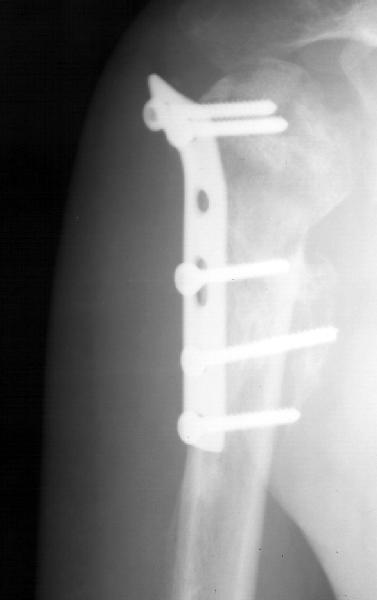

Мужчина 25 лет 16 августа 2002 г. в автоаварии получил перелом шейки плеча (снимок 1); 5 сентября в городской больнице выполнен остеосинтез пластинкой (снимок 2).К настоящему времени попал к нам на разработку ввиду выраженной контрактуры плечевого сустава. В течение последнего месяца беспокоят умеренные боли в области плечевого сустава, усиливающиеся при разработке, еще и торчит край пластинки. Нынешняя рентгенологическаякартина на снимках 3 и 4. Головка плеча уменьшается, сращение сомнительное.Кроме удаления пластинки, что еще на сегодня целесообразно сделать?Заранее спасибо.

Переломовывих плеча сложная проблема и технически не уверен как для коллег, но для меня сколько я не встречался, технически сложно *вытянуть* вывихнутую головку из-под впадины. Последнее время не применяю пластины для фиксации перелома, а использую спицы и проволочную петлю (тем более часто и густо спонгиозные винты не держатся в головке прочно).

Фиксация получается достаточно стабильная, правда мои заключения основаны только на клинических наблюдениях, возможности протестировать прочность фиксации в лабораторных условиях нет. Я не автор данного типа фиксации в основе его лежит принцип напряженной фиксации (Weber tension Band fixation). Когда-то у нас использовали фиксатор проф Сеппо при переломах

шейки бедра - принцип работы аналогичен, только менее громоздкие элементы конструкции и более доступные для применения в любых условиях.